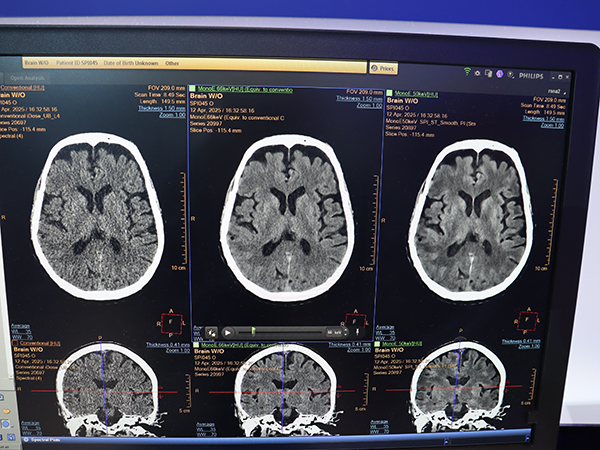

MRIでは,世界初の3.0TヘリウムフリーMRI「BlueSeal Horizon」(510 k Pending,薬機法未承認)が登場。一方,CTはスペクトラルCT「Verida」(510 k Pending,薬機法未承認)が発表された。Veridaに搭載される第3世代の二層検出器はAI画像再構成に最適化しており,AI画像再構成「Spectral Precise Image」により高解像度なスペクトラル画像を全身領域で取得できる。

フィリップスのCTの最上位機種となるスペクトラルCT「Verida」(510 k Pending,薬機法未承認)

AI画像再構成「Spectral Precise Image」と仮想単色X線画像(MonoE)により解像度とコントラストが向上(右)